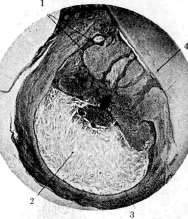

Рисунок 2. Кистовидная гранулема: 1 тяжи эпителия; 2 полость гранулемы, в содержимом которой находится большое количество кристаллов холестерина; 3 эпителиальная выстилка полости; 4 корень зуба.